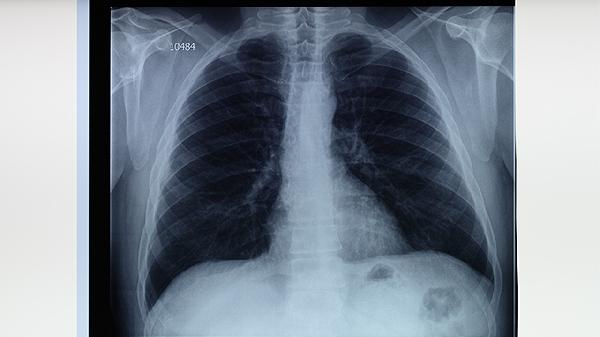

肺結(jié)核后的癥狀主要有咳嗽、咳痰、咯血、胸痛、發(fā)熱等。肺結(jié)核是由結(jié)核分枝桿菌感染引起的慢性傳染病,可能通過(guò)呼吸道傳播,患者需及時(shí)就醫(yī)治療。

肺結(jié)核患者應(yīng)注意休息,保證充足睡眠,避免過(guò)度勞累。飲食上應(yīng)加強(qiáng)營(yíng)養(yǎng),多攝入高蛋白食物如雞蛋、牛奶、瘦肉等,幫助恢復(fù)體力。保持居住環(huán)境通風(fēng)良好,避免到人群密集場(chǎng)所,減少傳播風(fēng)險(xiǎn)。嚴(yán)格遵醫(yī)囑完成全程抗結(jié)核治療,不可自行停藥,定期復(fù)查胸部影像學(xué)檢查。出現(xiàn)癥狀加重或藥物不良反應(yīng)時(shí),應(yīng)及時(shí)就醫(yī)調(diào)整治療方案。